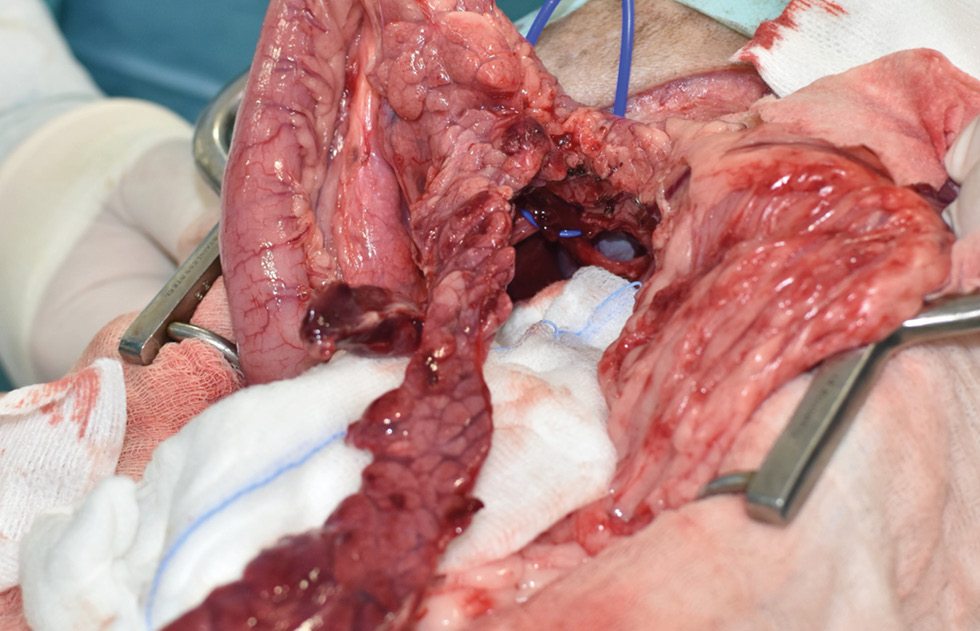

La cirugía de elección es la pancreatectomía parcial y la resección de losnódulos linfáticos (NNLL) centinelas (imágenes 3A-3I). La quimioterapia intracavitaria puede controlar la efusión por carcinomatosis secundaria, pero ofrece una respuesta paliativa de corta duración. La pancreatectomía completa o pancreaticoduodenectomía (técnica de Whipple), descritas en el perro, presentan altas tasas de morbilidad y mortalidad operatorias. La técnica de Billroth II es una opción paliativa a corto plazo en casos de obstrucción intestinal. En un estudio retrospectivo en 34 pacientes felinos con carcinoma pancreático exocrino primario la enfermedad se asoció con una historia previa de diabetes mellitus.35 El carcinoma pancreático exocrino canino se caracteriza por una alta tasa de metástasis y un pronóstico grave general.37

Imágenes 3A – 3I. Secuencia de imágenes quirúrgicas en un perro (con las imágenes del TC), durante una pancreatectomía parcial del lóbulo izquierdo y cuerpo del páncreas, usando un sellador vascular/tisular, por carcinoma pancreático.